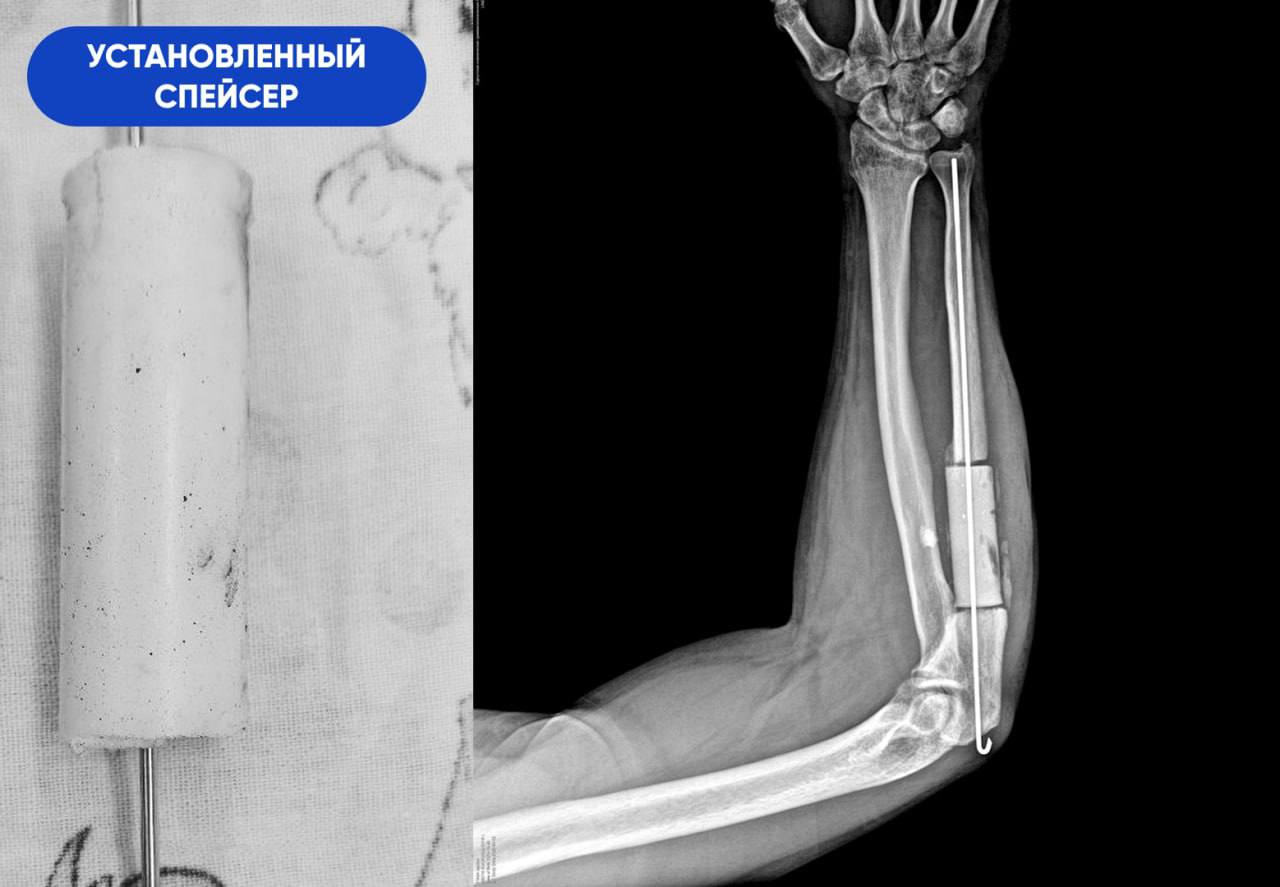

-В первую очередь нам необходимо было справиться с инфекцией. При свищевом остеомиелите ждать результата от обычной антибактериальной терапии бессмысленно. Воспалительный процесс разрушил кость на участке длиной 8 сантиметров. Этот фрагмент подлежал удалению в пределах здоровых тканей. На его место установили спейсер из антибиотика и костного цемента. Мы изготовили его самостоятельно в условиях операционной, по собственной технологии и индивидуальным размерам. Имплантат выполнял двойную задачу. Во-первых, это источник антибиотика в непосредственном очаге заражения. Во-вторых,- механическая поддержка для кости за счёт своей армирующей функции, - объясняет Сергей Глиняный.

Благодаря профессионализму и смекалке врачей, ещё на этапе лечения остеомиелита пациент впервые вновь начал двигать рукой и приступил к её разработке. Спейсер, зафиксированный на участке недостающего костного фрагмента, создавал эффект целостности кости на протяжении всех двух месяцев антибактериальной терапии. Однако самый ответственный этап был впереди.